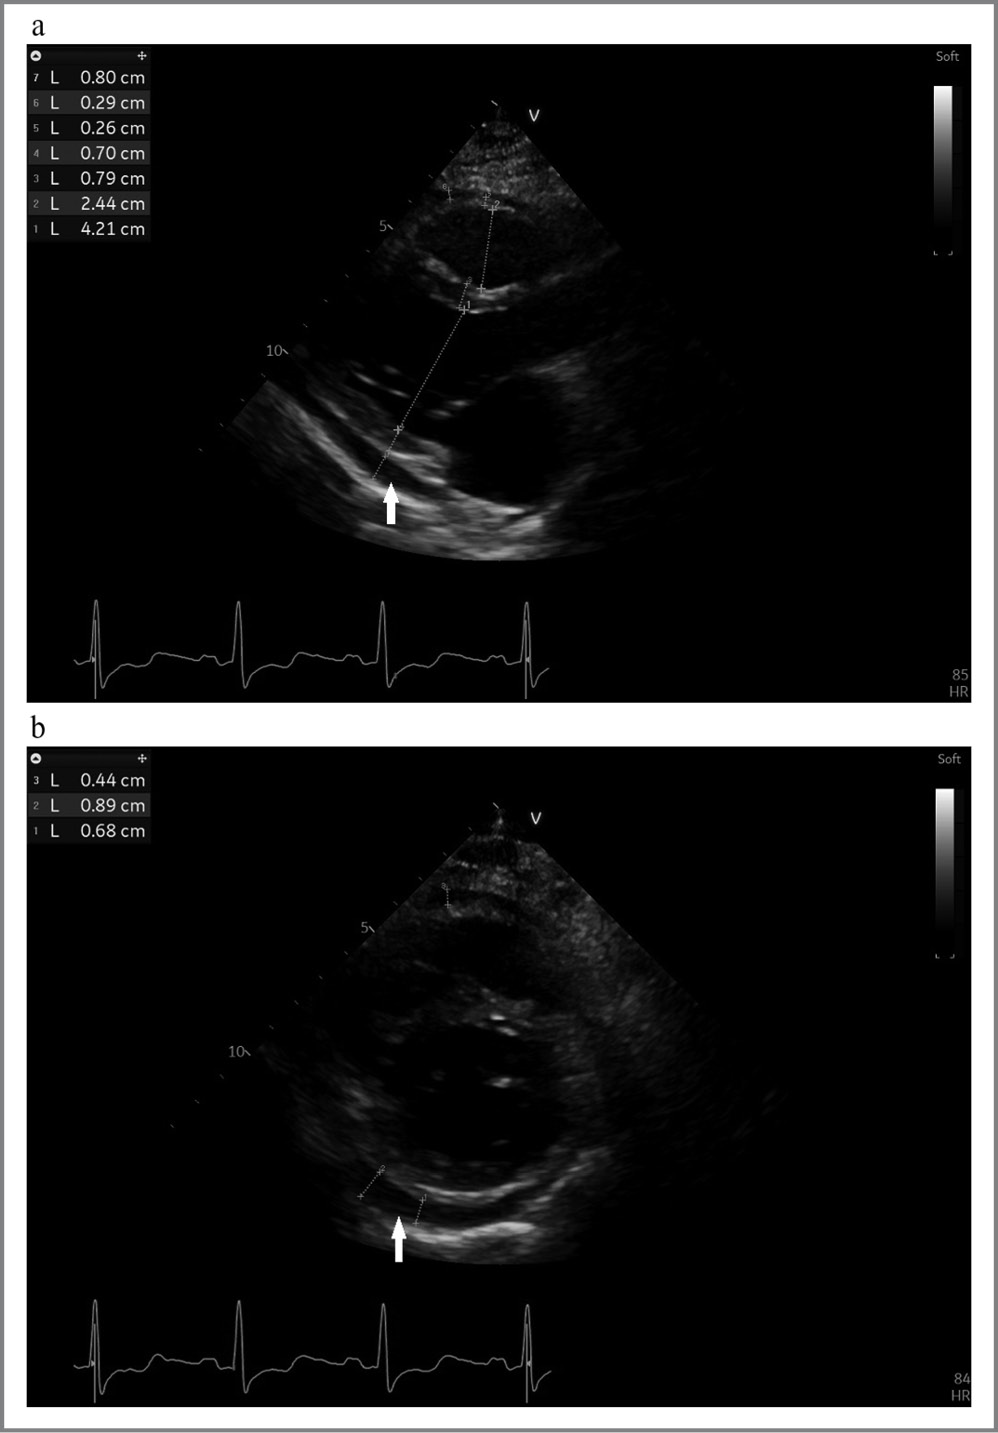

По данным трансторакальной ЭхоКГ: признаки констриктивно-экссудативного перикардита. Умеренное количество жидкости с признаками организации выпота. Сепарация листков перикарда в диастолу максимально до 1,2–1,7 см у боковой стенки ПЖ из субкостального доступа, до 1,0 см – у верхушки сердца, до 0,8 см – у задней стенки левого желудочка (ЛЖ) из парастернального доступа, до 0,5 см (выпот с признаками организации, гиперэхогенностью) – у правого предсердия, у нижней стенки ЛЖ и боковой стенки ЛЖ. Объем выпота составлял примерно 300 мл. Наблюдалось небольшое расширение левого предсердия. Нарушение продольной систолической деформации. ФВ – 55%. Признаки констриктивного перикардита: смещение межжелудочковой перегородки (МЖП) на вдохе в сторону ЛЖ; респираторная вариабельность диастолического потока на митральном клапане равна 25% (> 14,5%); отношение ретро- и антеградного потоков в печеночных венах в конце диастолы на выдохе составляло 1,28 (> 0,78); диастолическая скорость движения МЖП: e’ = 21 см/с (> 8 см/с); e’ МЖП/e’ бок. = 1,6 (> 0,9); признаки выраженного повышения давления в нижней полой вене, центральное венозное давление – 15–20 мм рт. ст.; гиперэхогенность и небольшое утолщение париетального листка перикарда – до 3–4 мм. Двусторонний умеренный гидроторакс (больше справа), небольшой асцит (рис. 3).

Рис. 3. Данные ЭхоКГ пациента К.: a – парастернальная проекция по длинной оси ЛЖ; b – апикальная проекция по короткой оси ЛЖ на уровне базальных сегментов.

Fig. 3. Patient K’s echocardiogram data: a – parasternal view along the long axis of the LV; b – apical view along the short axis of the LV at the level of the basal segments.